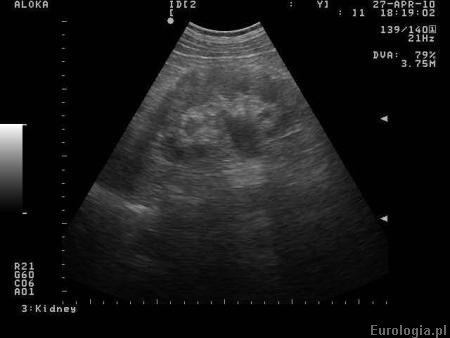

Fot.Poszerzony UKM nerki prawej w badaniu USG.

Poszerzony UKM nerki w badaniu USG brzucha. Stan po kolce nerkowej prawostronnej.